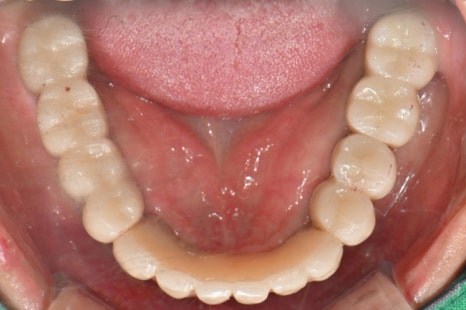

촬영:2024년1월9일

기존 틀니는 이제 아예 들어가지도 않는다며

어디 있는지도 모른다고 하셨습니다.

처음 보철하셨을 때, 치아 모양이 예뻐서

만족스러우셨을 것 같은데

보철 후 구강관리 및 사후관리가 많이 안되어진

모습으로 보입니다.

입안 상태를 보면

상악의 보철 위쪽으로 치조골이 녹아서 치아뿌리가 드러나있고

드러난 치아뿌리로는 치석과 염증이 뒤엉켜

수직적 잇몸흡수가 깊게 일어난 것을 확인할 수 있습니다.